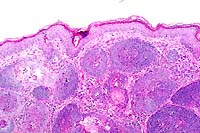

- Case III - C98-1029 (AFIP 2641899)

- Signalment: 1½ to 2-week-old male and female

Sprague Dawley rats.

- History: Three litters of Sprague Dawley rats ranging

in age from 1½ to 2 weeks developed diarrhea characterized

by yellow pasty to liquid feces. The perianal region of several

rats was stained with feces. Both sexes were equally affected.

- Gross Pathology: Gross examination of the infant rats

revealed distension of the small intestine and large intestine

with yellow fluid.

- Laboratory Results: Group D streptococcus was isolated

from the small intestine of affected rats.

- Contributor's Diagnosis and Comments: Small intestine: Streptococcus

enteropathy.

- Etiology: Streptococcus Group D.

- The bacteria lining the villi stained gram-positive and were

morphologically compatible with cocci. The diagnosis of streptococcal

enteropathy was based on:

1. Gram-positive cocci attached to the intestinal epithelium.

2. Streptococcus isolated as a predominate organism from the

small intestine.

3. Lack of inflammation or necrosis associated with the bacteria.

40x

obj

- Case 13-3. Small intestine. Abundant basophilic cocci

line the mucosal epithelium of some crypts.

-

- AFIP Diagnosis: Small intestine: Numerous luminal

epithelium adherent cocci, Sprague Dawley rat, rodent.

- Conference Note: Since 1985, there have been several

reports of an enteropathy in suckling neonatal rats caused by

enteric streptococci. Infected neonatal rats are often abnormally

small, have distended abdomens, poor haircoats, and fecal soiling

around the perineum. The disease is not associated with mortality.

Histologically, numerous epithelium adherent enterococci are

found along the intestinal villi with no other microscopic changes

or inflammation.